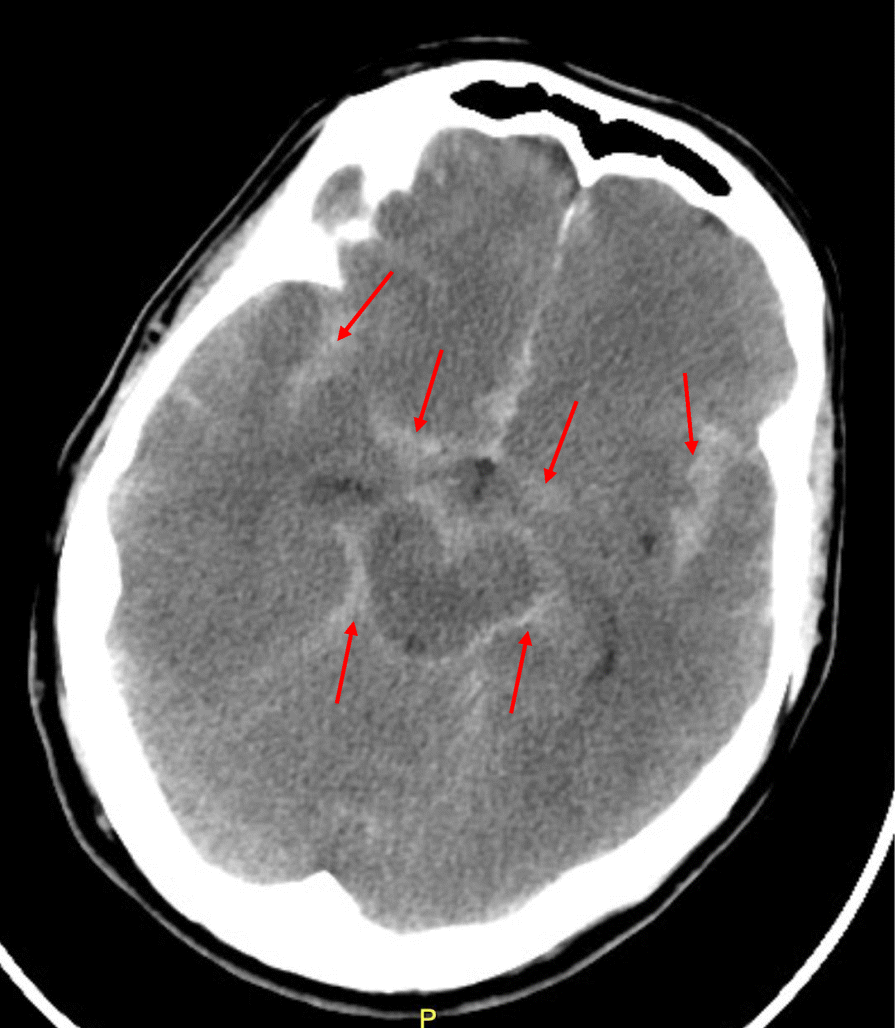

Fig. 1From: Subarachnoid hemorrhage in the emergency departmentSubarachnoid hemorrhage on CT headBack to article page